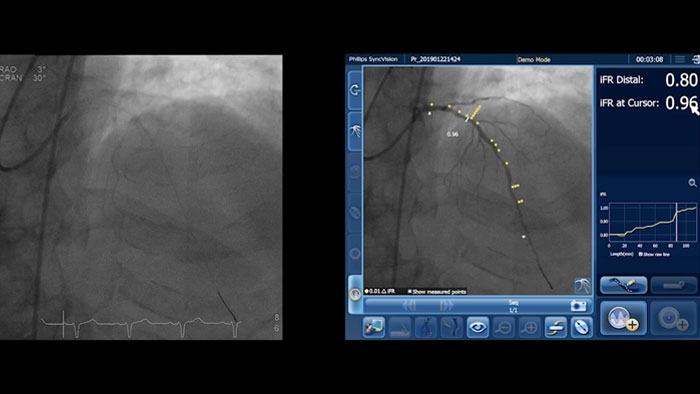

血管造影だけでは、病変の位置を特定するには不十分です。当社製品は、iFR¹,²,³の値を血管造影図にコレジストレーションすることで、高度なPhysiology評価が可能になり、血管のどの位置で虚血を起こしているのか正確に見たうえで、治療戦略を決定することができます。

iFR コレジストレーションでは血管拡張剤が不要で、時間のかかるプルバック装置の操作もなく、憶測ベースでの評価をなくします。

iFR コレジストレーションによる PCI を計画する際には、虚血があるかどうかだけでなく、どこにあるかを理解する必要があることを、Allen Jeremias 博士が説明します。

iFR コレジストレーションによる PCI 実施方法の変革 PCI を計画する際には、虚血があるかどうかだけでなく、どこにあるかを理解する必要があることを、Allen Jeremias 博士が説明します。